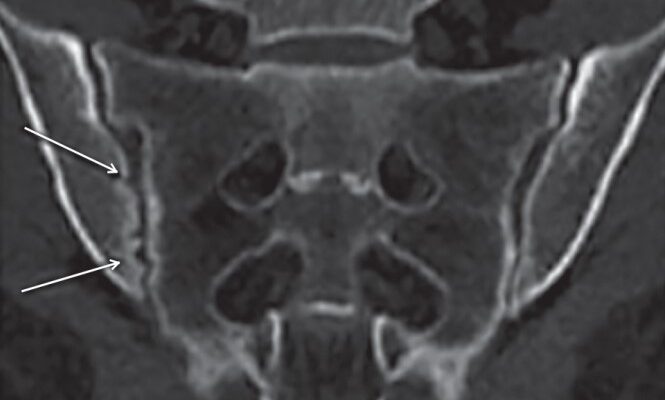

Лікарі, ті маги білих халатів, бачать сакроілеїт через рентген чи МРТ. Не ду́мають два рази. Але іноді цього замало. Хто точно скаже? Правильно, справжній спеціаліст з суглобами. Навіть якщо ти не віриш у медицину, довірся. Правда на їхньому боці.